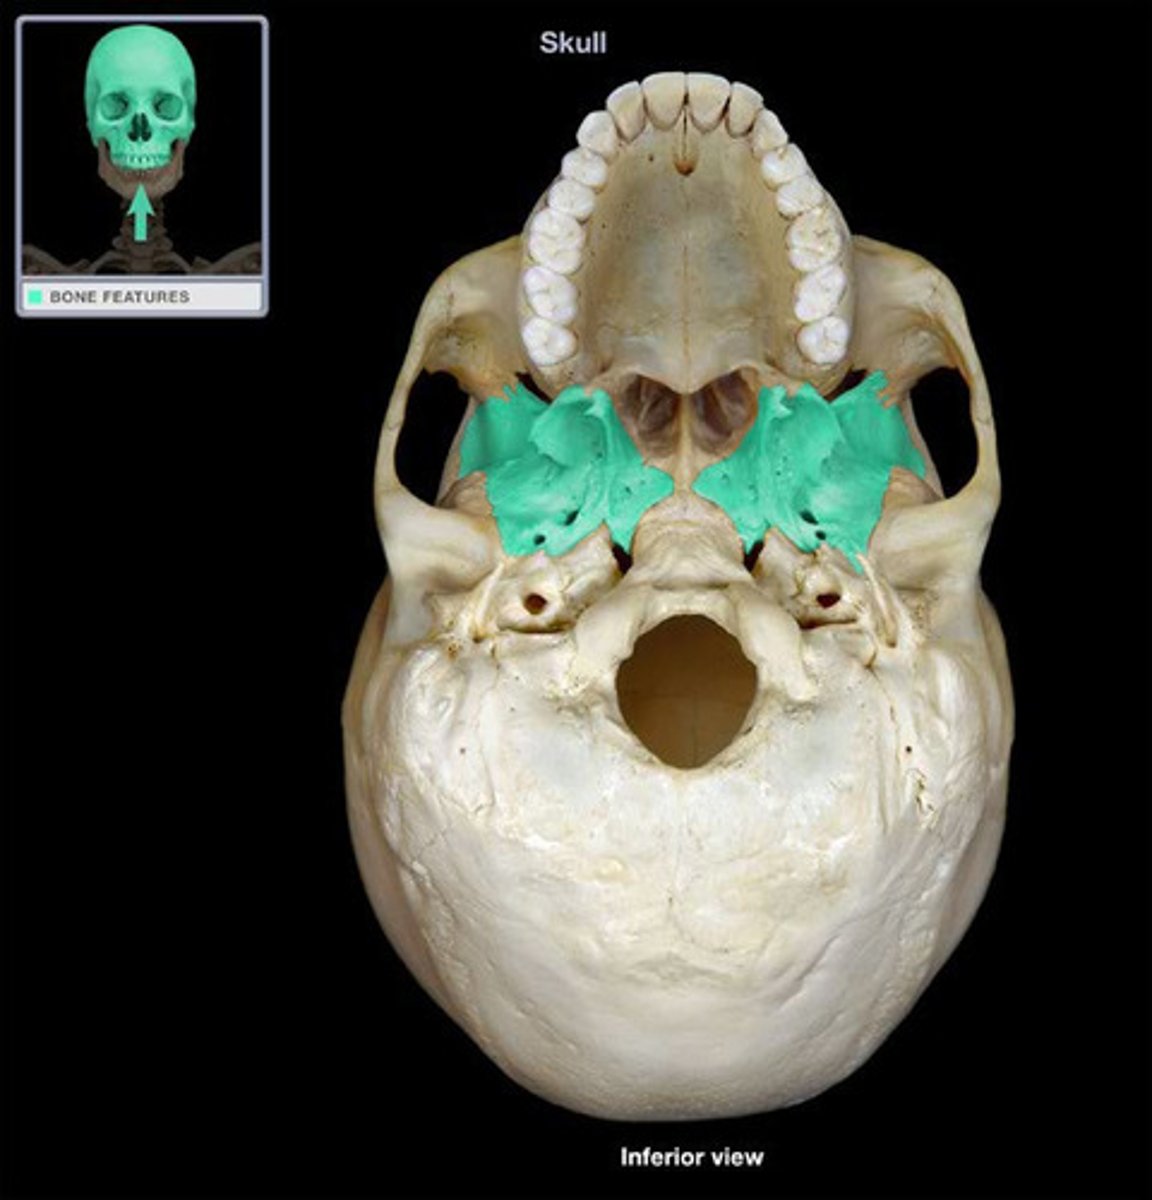

Sphenoid

Sphenoid

Sphenoid

Sphenoid

Palantine Bone